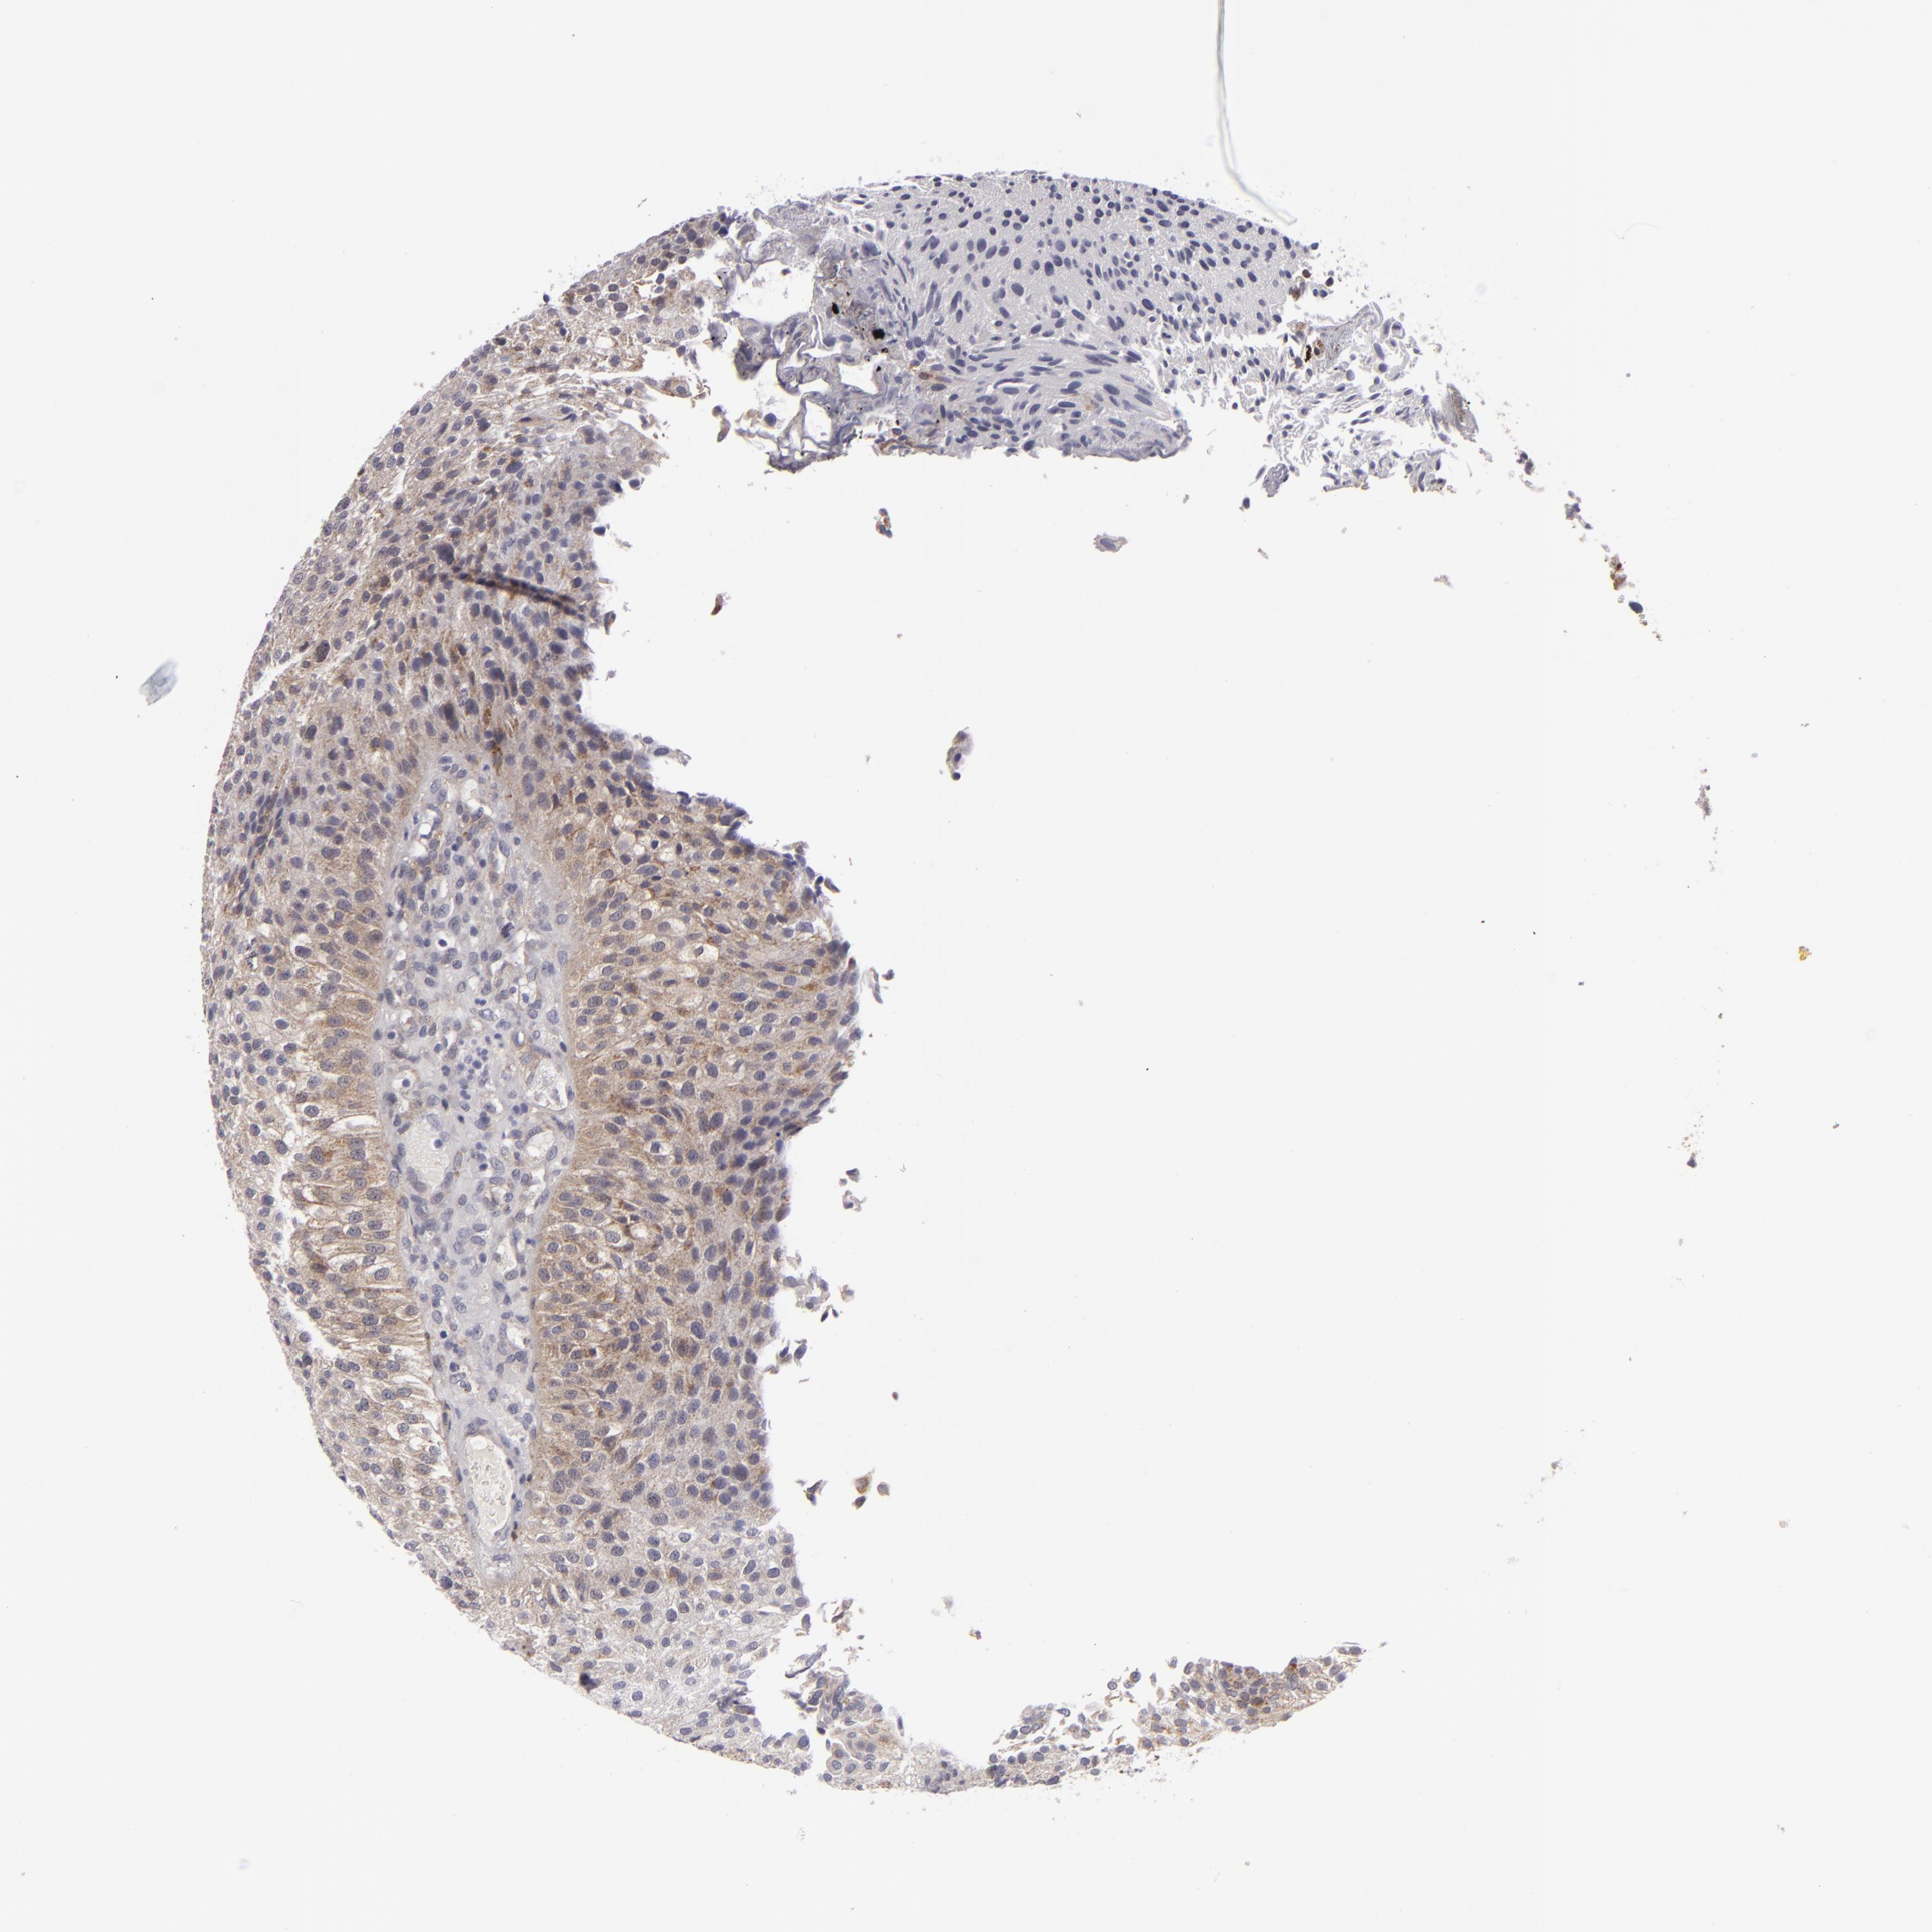

UROTHELIAL CANCER - Protein expressioni

A mouse-over function shows sample information and annotation data. Click on an image to view it in a full screen mode. Samples can be filtered based on level of antibody staining by selecting one or several of the following categories: high, medium, low and not detected. The assay and annotation is described here.

Note that samples used for immunohistochemistry by the Human Protein Atlas do not correspond to samples in the TCGA dataset.

Antibody stainingi

Antibody staining in the annotated cell types in the current human tissue is reported as not detected, low, medium, or high, based on conventional immunohistochemistry profiling in selected tissues. This score is based on the combination of the staining intensity and fraction of stained cells.

Each image is clickable and will lead to virtual microscopy that enables deeper exploration of all samples and also displays staining intensity scores, fraction scores and subcellular localization as well as patient and tissue information for each sample.

Antibody HPA010926

Antibody CAB002148

Urothelial carcinoma, Low grade

Urothelial carcinoma, High grade

Adenocarcinoma, NOS